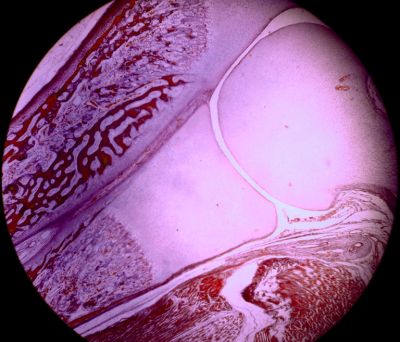

Developing bone - histology slide

This is a histology slide of a developing long bone.

Histology slide courtesy of Florida State University.